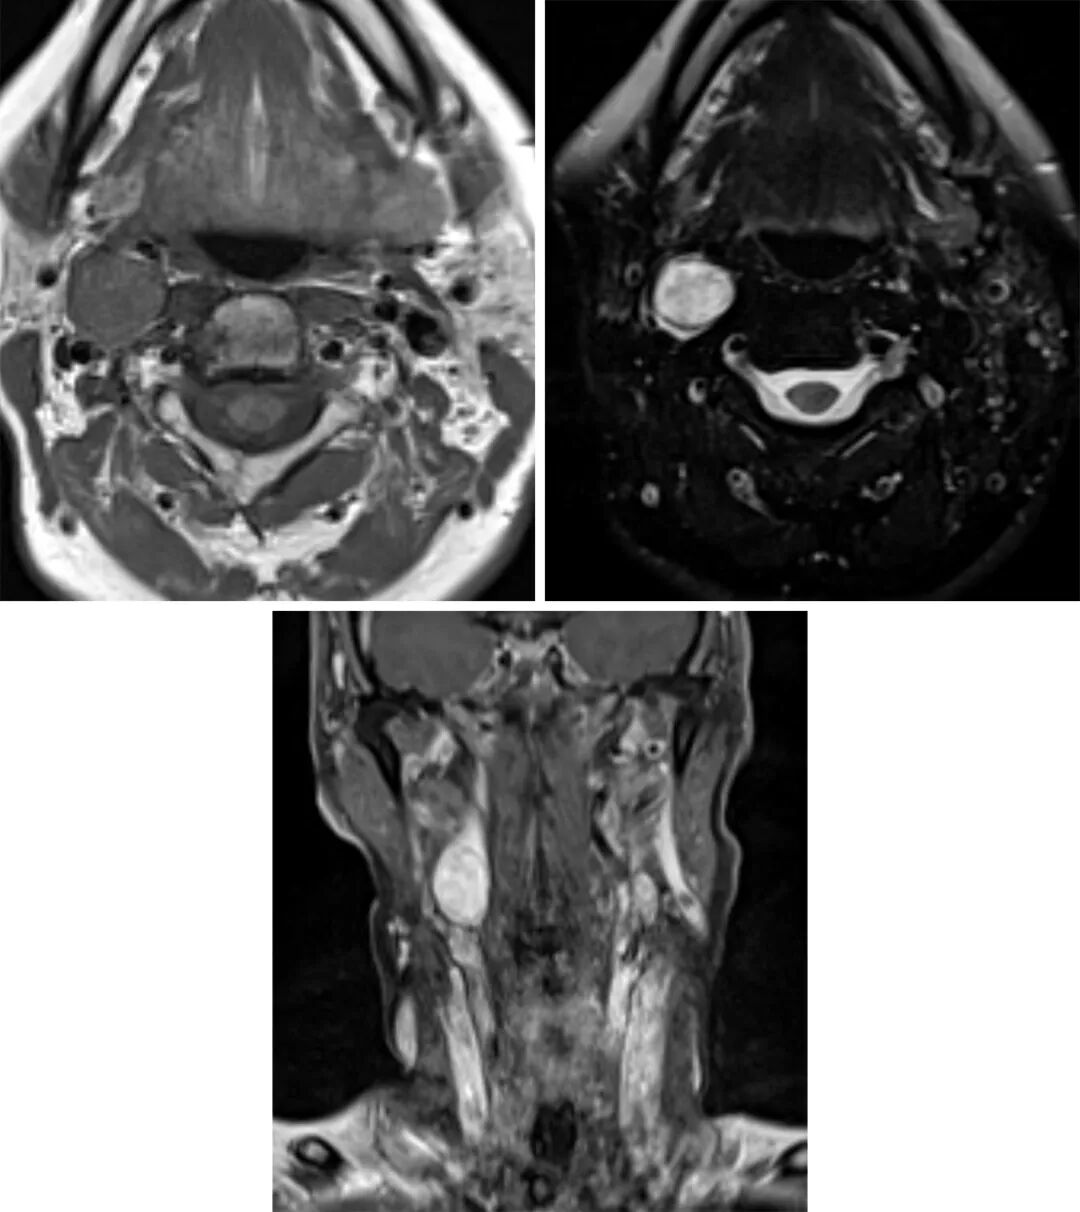

图1. T1加权相(左上)提示低信号占位扩张至颈内动脉及颈外动脉,这是颈动脉体副神经节瘤的高发位置,在T2加权相表现为高信号,由于其血流量较高,因此常伴有血管流空现象(右上)。由于肿块血供丰富,因此强化明显(下图)。

“椒盐征”为MRI特征性表现

T1高信号“盐”是由于亚急性出血,低信号的“椒”是由于动脉血管流空现象(在大肿瘤中更常见)

T1加权相:呈不均一信号,可伴有亚急性出血的高信号区域(“盐”),这是一种不常见的表现,存在低信号的血管流空现象(“椒”)

T2加权相:呈不均一高信号, 低信号的血管流空现象

T1增强加权相:早期增强明显